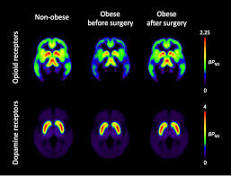

Medical Xpress

Finnish researchers found that obesity surgery and concomitant weight loss normalized brain's opioid neurotransmission, which is involved in ...